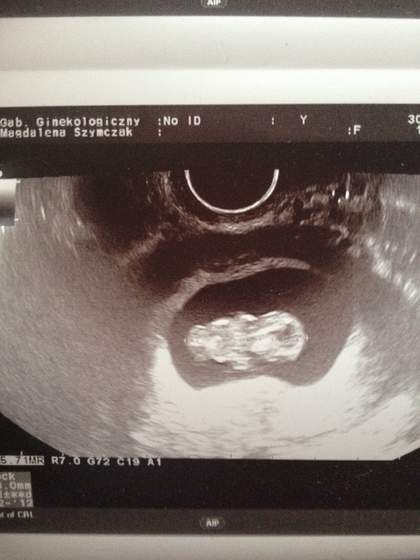

Pecherzyk jest ładny, okrąglutki, ma 11,2mm(ciaza młodsza o 6 dni) czyli urósł te przepisowe 4mm w 4 dni.zarodka jeszcze nie widac.